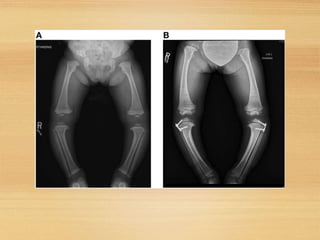

Physiological… Pathological

In ligamentous laxity notelat.Widening

Of knee joints

In Blount angulation at med.tib

metaphysis

In coxavara ,angulation at the neck shaft

level

In cong. Pseudarthrosis of tibia,the

angulation is in the distal⅓